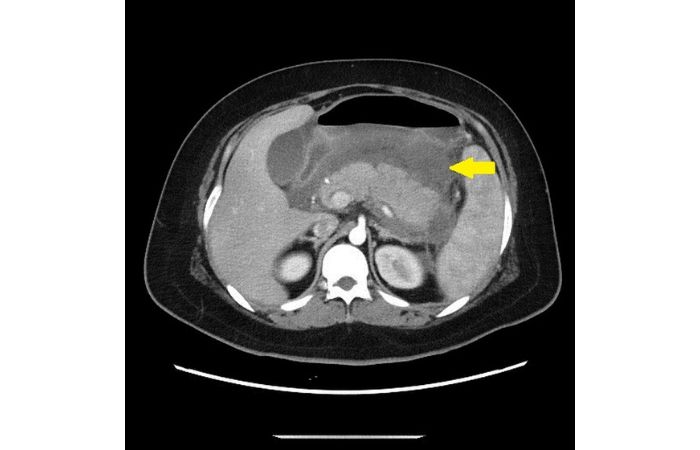

血脂肪過高引致急性胰臟炎,胰臟發炎腫脹,胰臟周圍也呈現發炎狀態。(圖:臺北慈濟醫院) (文:廖唯晴 新北報導 慈濟基金會文史處葉臻編輯 2024/05/31)